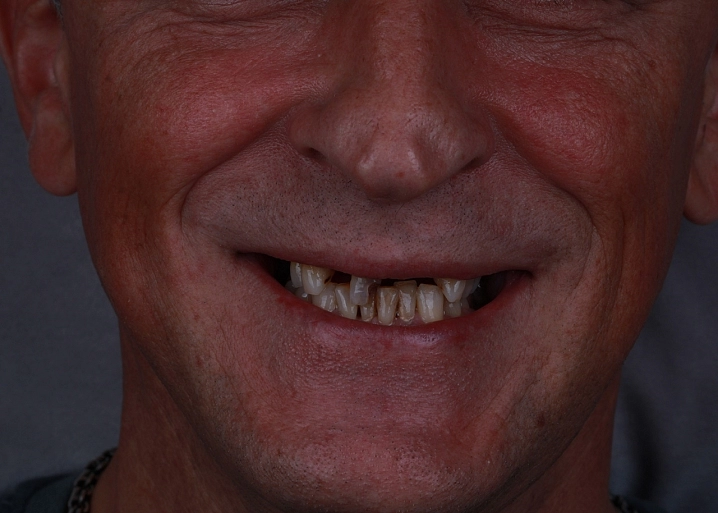

На первичном осмотре в клинике стоматолог определяет степень разрушения зуба. Проводится КТ диагностика для понимания состояния корня зуба, каналов. Фотопротокол для оценки исходной ситуации. Сама консультация проходит в консультативной комнате, где доктор наглядно показывает пациенту его клиническую ситуацию в полости рта и объясняет всё о предстоящем лечении. Определяется из какого материала и каким методом будет изготавливаться будущая вкладка и назначается эндодонтическое лечение каналов зубов, при необходимости. Составляется план лечения.